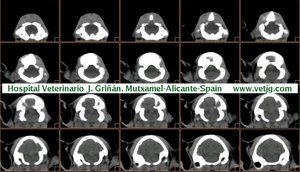

imágenes de TC en el gato | |||||||||||

Tomografía computarizada helicoidal |